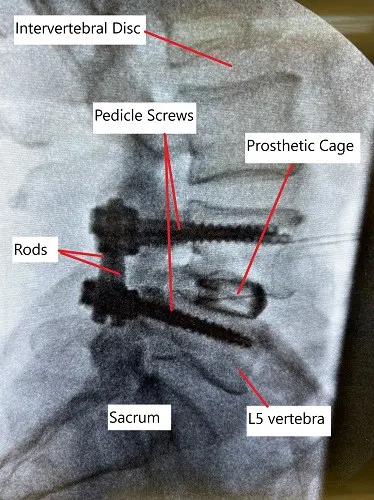

- Spinal Fusion: A procedure that joins two or more vertebrae together using bone grafts and hardware (screws, rods) to stabilize the spine. This is often done in cases of spinal instability, spondylolisthesis, or multiple disc herniations.

- Spinal Fusion:

- Non-fusion (Non-union): In some cases, the bones may fail to fuse properly, requiring additional surgery.

- Hardware Complications: Broken or misaligned screws/rods may require revision surgery.

- Adjacent Segment Degeneration: Increased stress on adjacent vertebrae can lead to further degeneration.